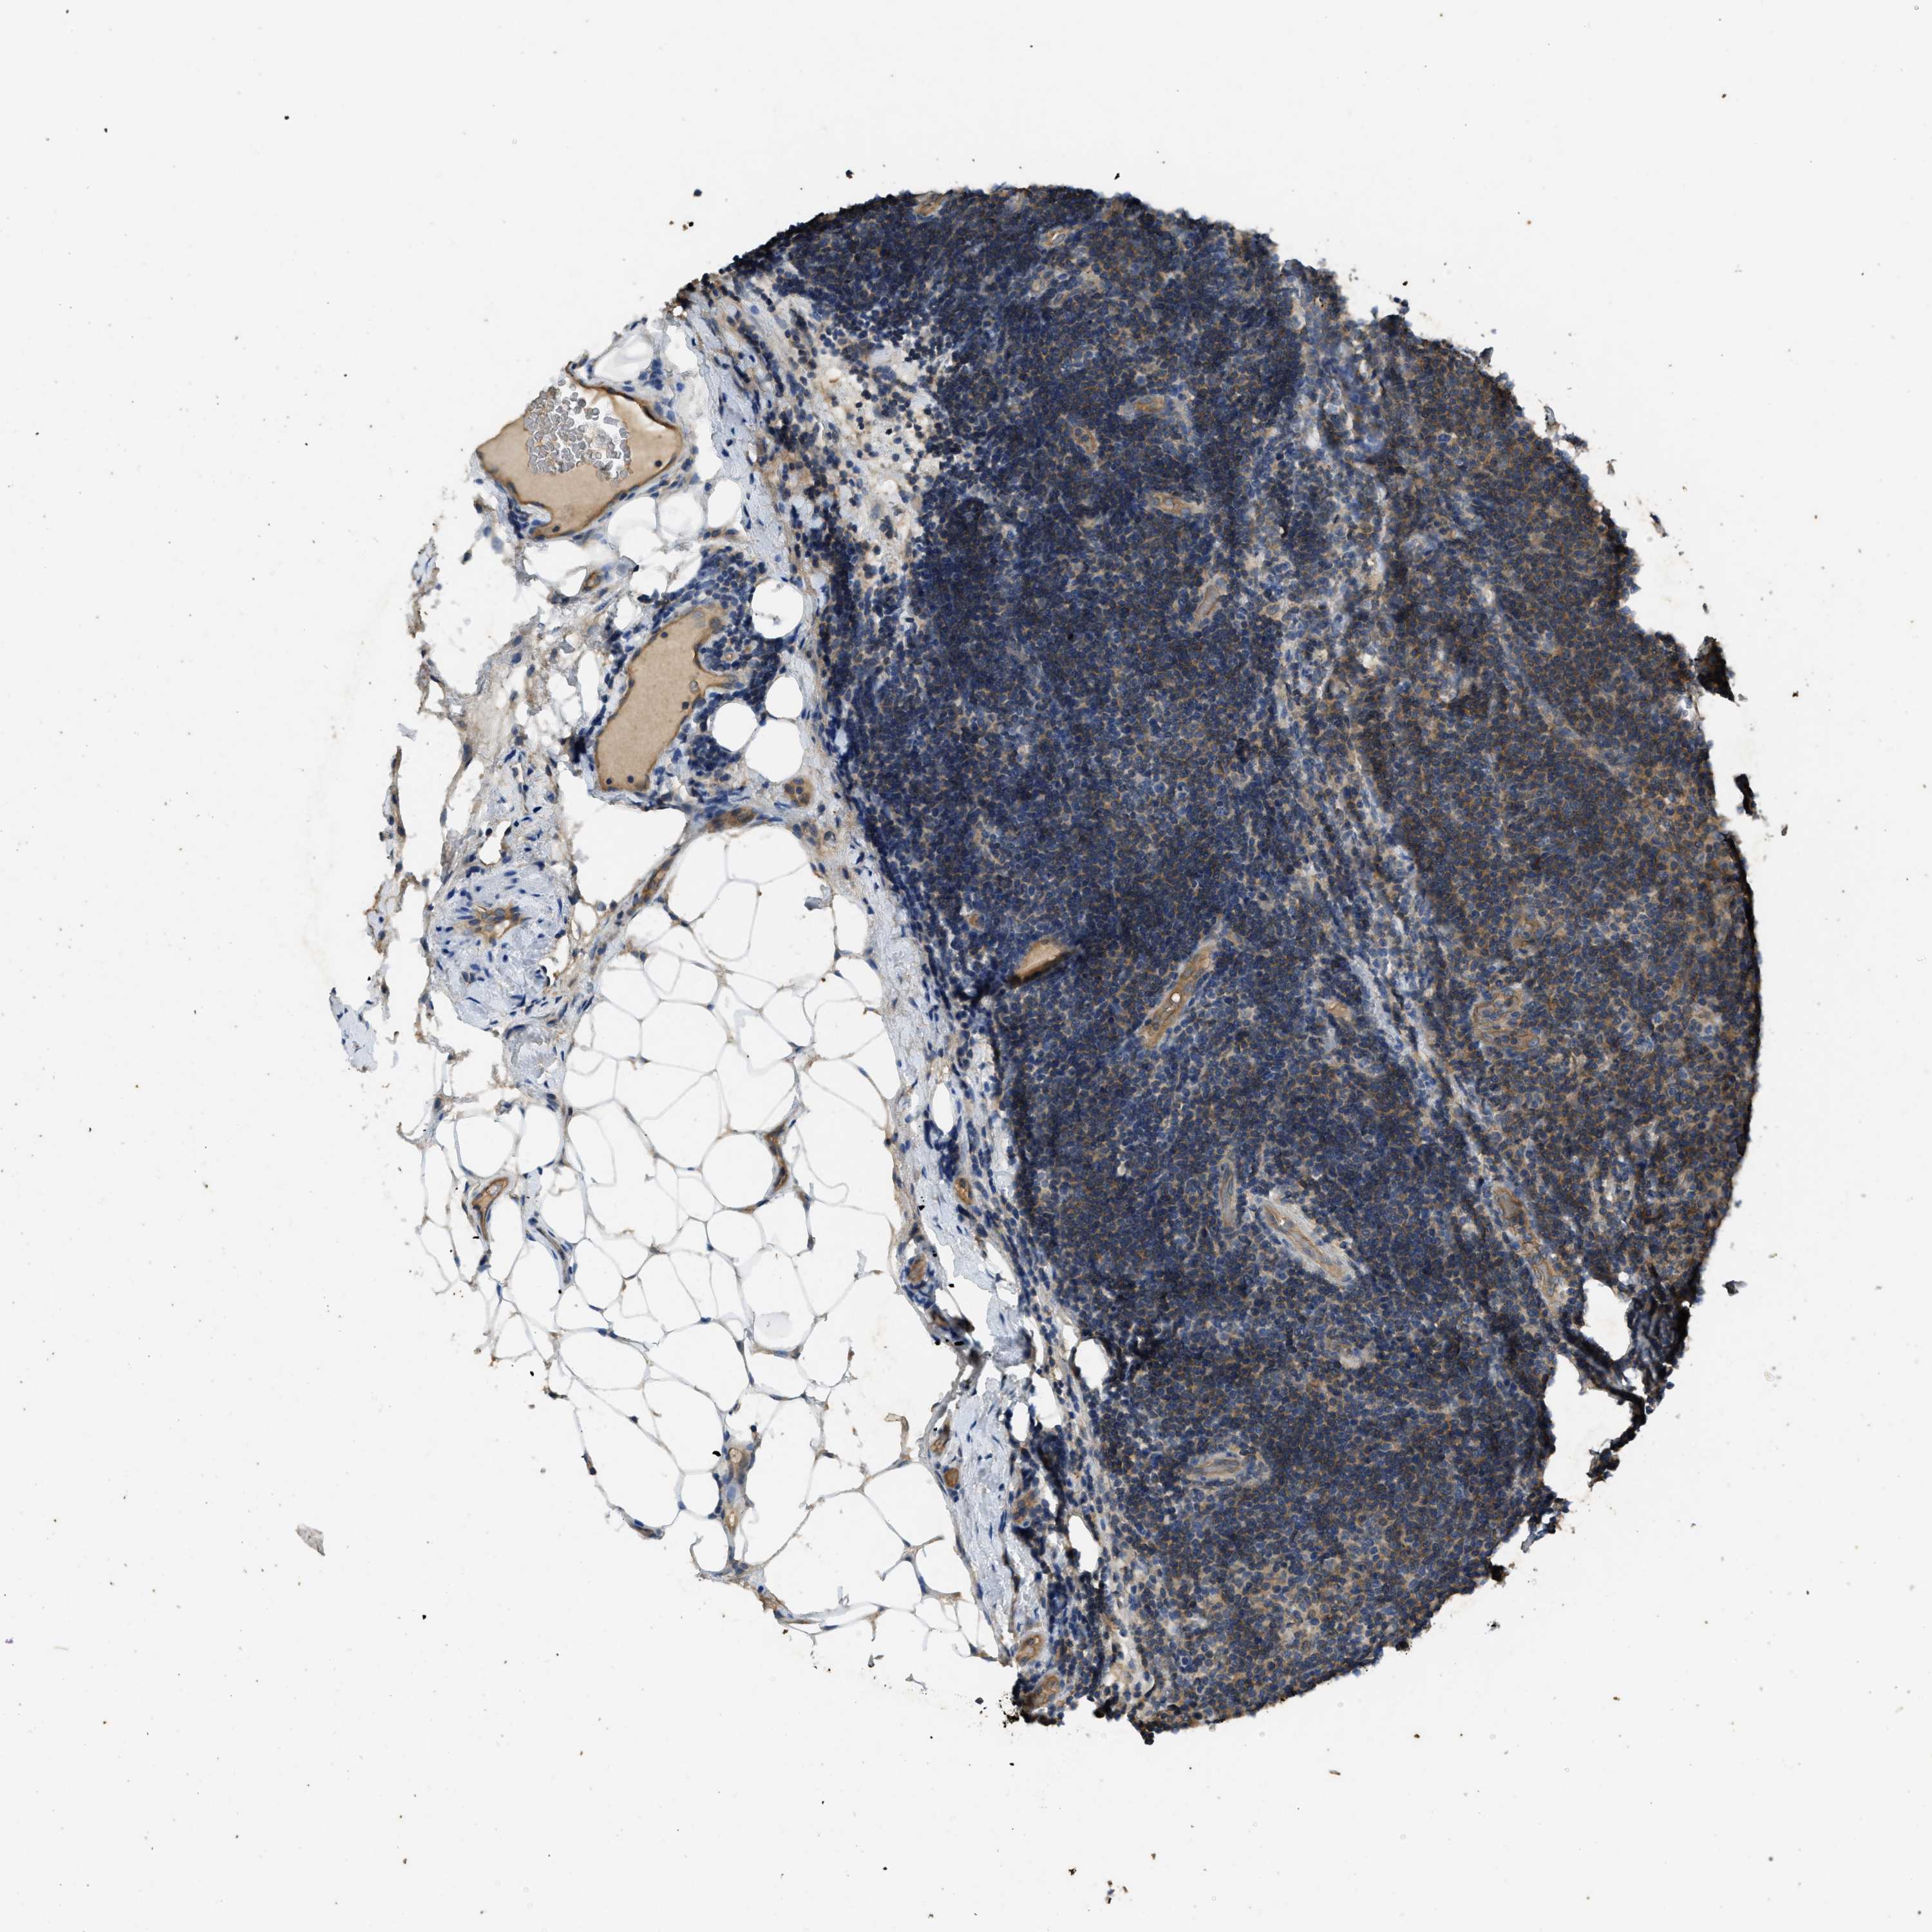

CANCER LYMPHOMA Show tissue menu

LYMPHOMA - Protein expressioni

A mouse-over function shows sample information and annotation data. Click on an image to view it in a full screen mode. Samples can be filtered based on level of antibody staining by selecting one or several of the following categories: high, medium, low and not detected. The assay and annotation is described here.

Antibody stainingi

Antibody staining in the annotated cell types in the current human tissue is reported as not detected, low, medium, or high, based on conventional immunohistochemistry profiling in selected tissues. This score is based on the combination of the staining intensity and fraction of stained cells.

Each image is clickable and will lead to virtual microscopy that enables deeper exploration of all samples and also displays staining intensity scores, fraction scores and subcellular localization as well as patient and tissue information for each sample.

Antibody HPA012778

Antibody CAB018581

Staining

High

Medium

Low

Not detected

Intensity

Strong

Moderate

Weak

Negative

Quantity

>75%

75%-25%

<25%

None

Location

Nuclear

Cytoplasmic/membranous

Cytoplasmic/membranous,nuclear

Hodgkin's disease, NOS

Malignant lymphoma, non-Hodgkin's type, High grade

Malignant lymphoma, non-Hodgkin's type, Low grade